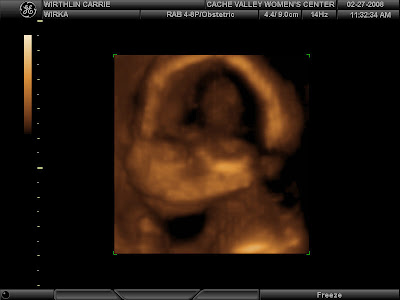

WELCOME Baby Boy Wirthlin #4!!!!!!!

Mark and I went for my 20 week ultrasound today and the first thing the tech said is "oh you came on a good day, I am having a girl day. Monday was a boy day and today is a girl day." Well we proved her theory wrong! I had a bitter-sweet moment for two seconds and now I am back in the "yeah baby mode". This boy is going to need all new clothes anyways after three boys have went through everything. I guess I haven't got how to parent boys because I keep getting more chances. Mark said "now we have to think of another boy name!" So that should be interesting. The baby was healthy and everything looked great. He was quite shy and didn't want his picture taken. For that reason, we did not get a very good profile, but of course, he looks exactly like the other three and their profile in the ultrasounds. Maybe I need to get a girl dog so I am not so out numbered.